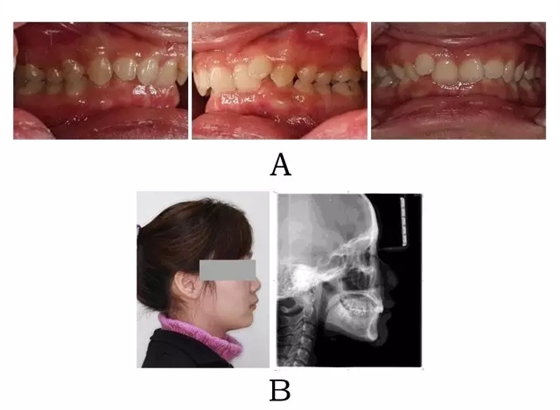

面型前突,面下部高度不足,頦唇溝較深??趦?nèi)表現(xiàn)為上頜骨源性前突,上前牙代償性直立或輕度唇傾;下頜后退伴深覆合深覆蓋,磨牙系遠(yuǎn)中關(guān)系。頭顱側(cè)位片下頜骨體部呈“長方形”,頦部形態(tài)較好(圖4-1)。

圖4-1:混合I型突面畸形臨床表現(xiàn)及頭顱側(cè)位影像特征。

(A)齒槽與牙列特點(diǎn) (B)側(cè)貌與影像對比

Figure 4-1. Clinical manifestation and cephalometric image for merged skeletal and mandibular positional prognathism (Type I). (A) Alveolar and dentition specifics. (B) Facial profile and radiographic image.